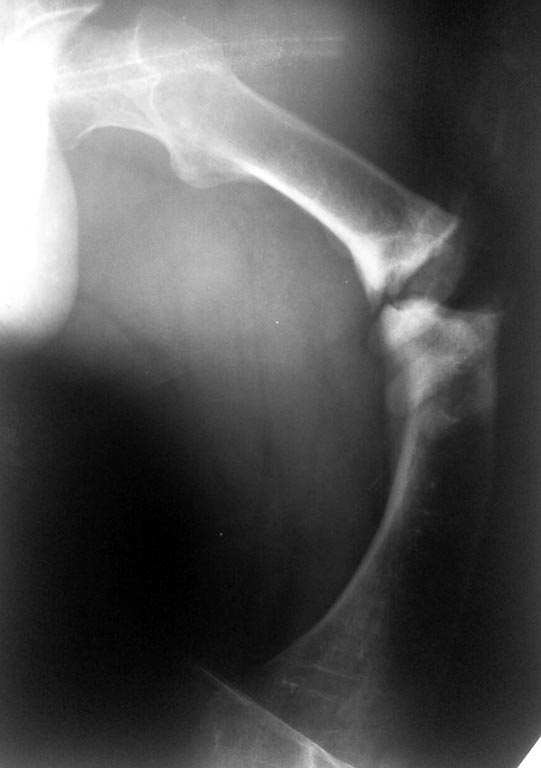

Maxim,

А действительно это Блаунт? Может быть ахондроплазик или дисхондроплазик. 2 недели назад оперировал, поставил обычную компрессионную пластину АО и никакой резекции. И у моего пациента выглядел как псевдартроз. Еще раз порасспрашивайте б-го, может удлиняли бедро? Не забыть бы в понедельник рентгены сфоткать и отправить Вам

А про nail даже и не думайте - канал кривой-косой, очень широкий и короткий